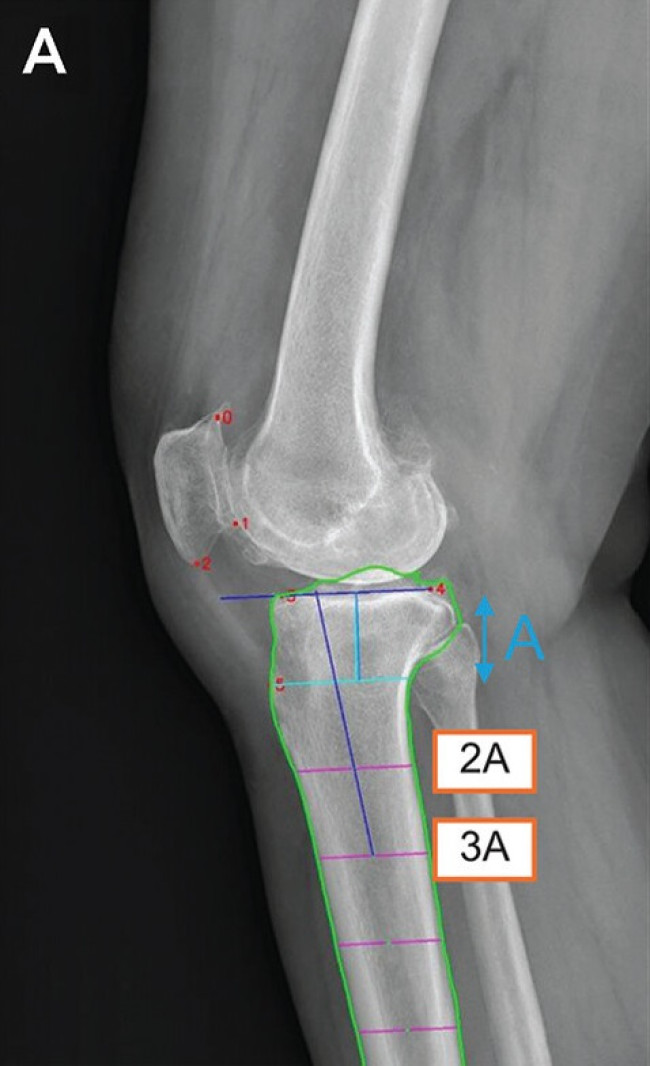

이에 연구팀은 무릎 엑스레이 영상에서 무릎뼈의 해부학적 기준점 6곳을 자동으로 인식하고, 기준점을 이용해 경골의 기울기를 계산하는 AI 모델을 개발했다.

딥러닝 모델의 경골 후방 경사각 측정 메커니즘딥러닝 모델의 경골 후방 경사각 측정 메커니즘.  AI 모델은 무릎뼈의 6개의 해부학적 기준점(빨간 점)을 자동 인식한 후, 경골의 관절선과 중심축(파란 선)을 결정해 경골 후방 기울기를 계산한다. 2025.08.26. [서울대병원 제공. 연합뉴스 사진]